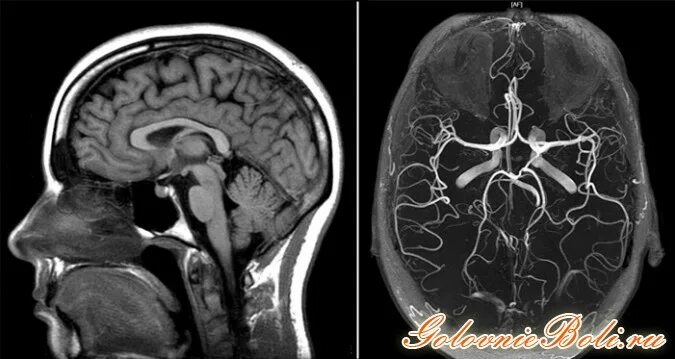

Чем отличается мрт от мрт с контрастом